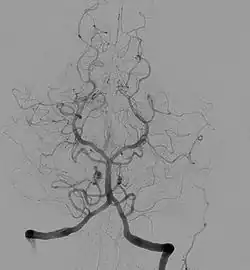

Image produite par angiographie cérébrale.

Angiographie cérébrale

Elle est l’application de la méthode de l’angiographie au niveau cérébral. Elle est utilisée en diagnostique et en interventionnelle. Les principales pathologies sont des dilatations des vaisseaux (anévrismes), le rétrécissement de vaisseaux (sténose) ou le blocage.

Elle est utilisée pour diagnostiquer des anomalies sur les vaisseaux sanguins du cerveau ou menant au cerveau (carotides). Ces différentes pathologies vasculaires peuvent être : un blocage (thrombose) ou un rétrécissement (sténose) d’un vaisseau, un anévrisme, une malformation artério-veineuse. On peut réaliser cet examen en préopératoire afin d’observer le système d’irrigation du cerveau. L’angiographie cérébrale permet également de diagnostiquer des pathologies non directement liées au système vasculaire mais ayant une influence sur celui-ci. Elle permet de visualiser des tumeurs, des œdèmes, des hernies, des vasospasmes, l’augmentation de la pression intracrânienne et l’hydrocéphalie.

L’apparition de nouvelles techniques d’imagerie non invasives a réduit l’importance de l’utilisation de l’angiographie cérébrale. On peut citer l’angioscanner, l’échographie doppler, l’angio-imagerie par résonance magnétique. Mais l’angiographie peut être recommandée après un examen précédent, afin d’apporter des informations complémentaires qui ne sont pas visibles par les nouvelles technologies. L’angiographie cérébrale reste l’examen le plus précis dans l’étude de la morphologie des vaisseaux sanguins, ainsi que pour fournir des données dynamiques sur la circulation.